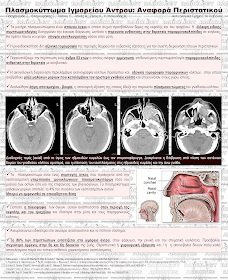

Πλασμοκύττωμα Ιγμορείου Άντρου

Πασχαλούδη Σ., Φλαμουράκης Γ., Τασίου Θ., Τσικές Α., Ζέκος Κ., Κοπανούδης Α.

Ακτινολογικό Τμήμα Γ.Ν. Καβάλας